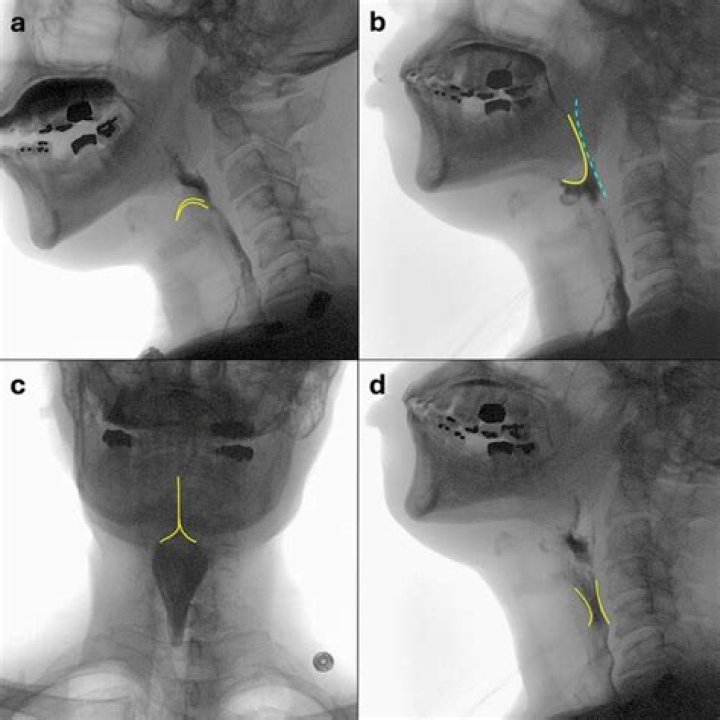

What is the penetration aspiration scale?

Abstract. The development and use of an 8-point, equal-appearing interval scale to describe penetration and aspiration events are described. Scores are determined primarily by the depth to which material passes in the airway and by whether or not material entering the airway is expelled.

How do you perform a barium swallow?

To do a barium swallow, you swallow a chalky white substance known as barium. It’s often mixed with water to make a thick drink that looks like a milkshake. When it’s swallowed, this liquid coats the inside of your upper GI. Barium absorbs X-rays and looks white on X-ray film.